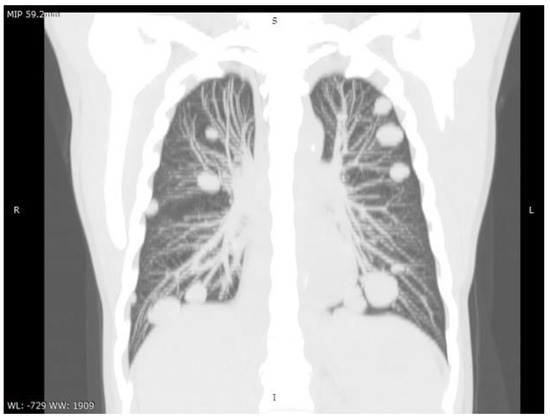

Hepatocarcinoma with Tumor Thrombus Occupying the Right Atrium and Portal Vein in a Patient with Hereditary Hemochromatosis and Liver Cirrhosis

Case report